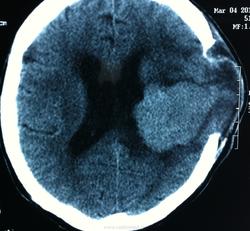

КТ контроль после операции.

Мне видится так. Иначе в данной локализации просто неоткуда расти оболочечной опухоли. На контрольной КТ, после декомпрессии, когда срединные структуры стали действительно срединны, правое обызвествленное сосудистое сплетение видно отчетливо, а левое, где оно? Ведь если бы образование компремировало, то после операции, когда часть мозга пролабировало в трепанационное отверстие мы бы увидели и левое сосудистое сплетение, но оно интимно связано с образованием и даже "потянулось" за ним в сторону декомпрессионного отверстия, потому что это и есть "росток" откуда выросла опухоль.